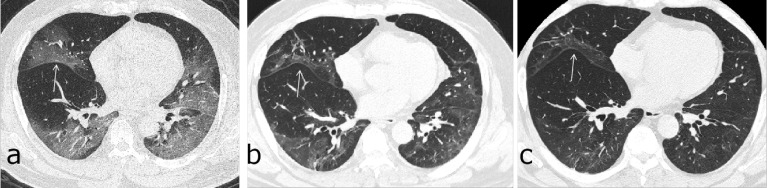

Figure 6:

Serial CT scans of a 52-year-old man with severe COVID-19 pneumonia. (a) The axial thin-section CT scan obtained on day 8 after symptom onset showed multiple ground-glass opacities (GGOs) bilaterally, with a slight traction of the right interlobar pleural (arrow). (b, c) Scans obtained on days 79 and 149, respectively, showed continuous absorption of previous opacifications, with the progression of interlobar pleural traction.